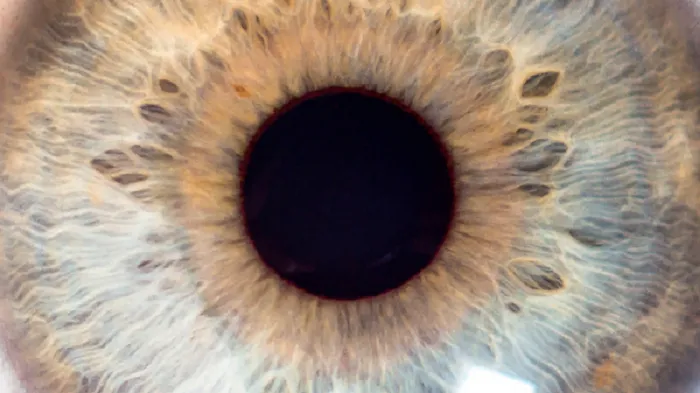

La rétine est une membrane qui tapisse le fond de l’œil. Elle est composée de millions de cellules nerveuses sensorielles ou visuelles. Elle reçoit les images des objets que l’œil regarde. Les images qui arrivent sur la rétine sont ensuite envoyées au cerveau, qui les analysent.

La macula, située au centre de la rétine, est la partie qui offre la meilleure acuité visuelle. Elle nous permet de voir avec une plus grande précision et de percevoir les couleurs. C’est aussi grâce à la macula que nous pouvons fixer les objets, lire, reconnaître des visages ou enfiler une aiguille.